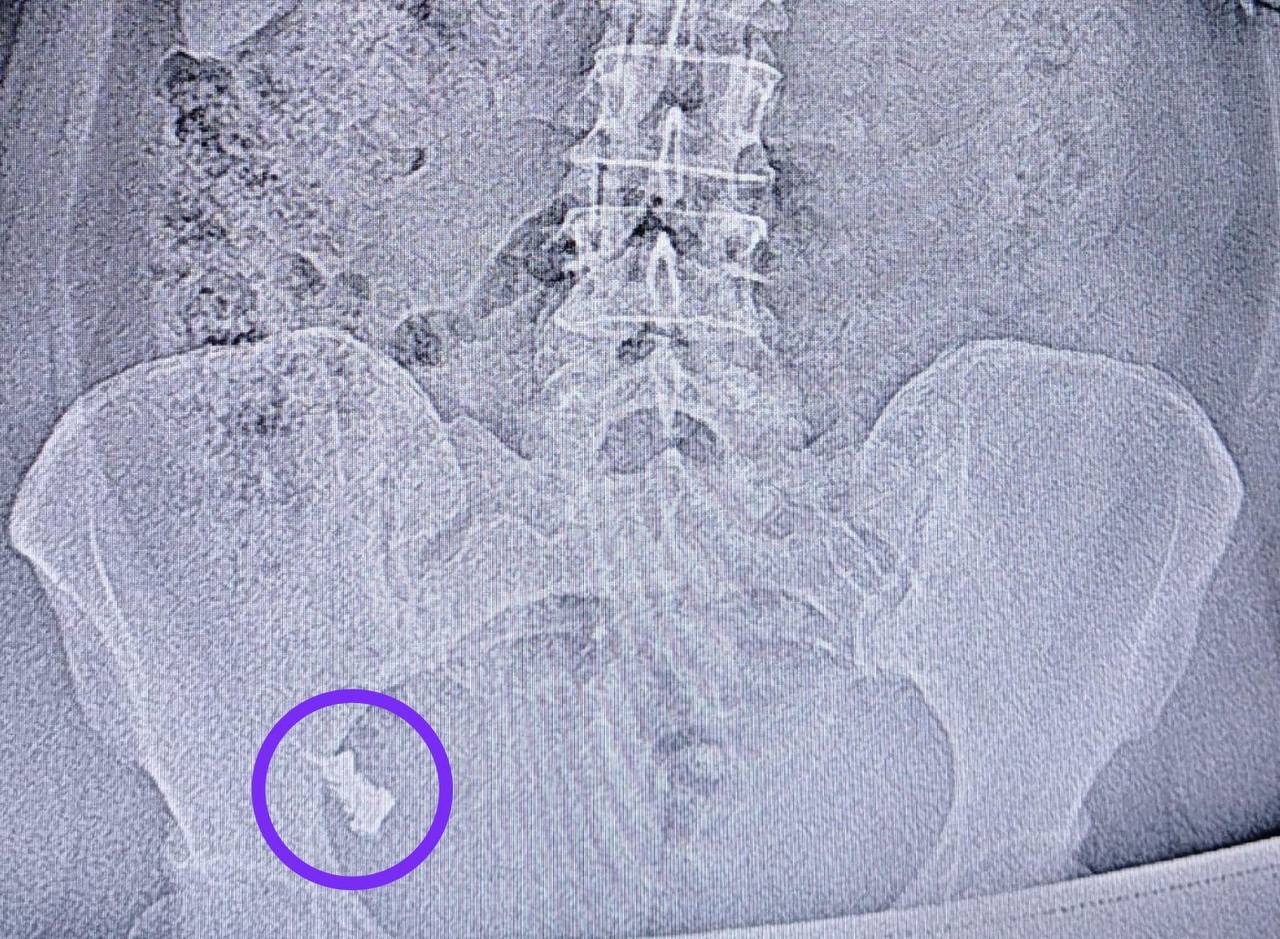

Пациентка поступила в хирургическое отделение №1 РКБ через неделю после проглатывания зубного протеза. Инородное тело застряло в зоне перехода тонкой кишки в толстую. Ранее женщина отказывалась от проведения фиброгастродуоденоскопии и госпитализации.